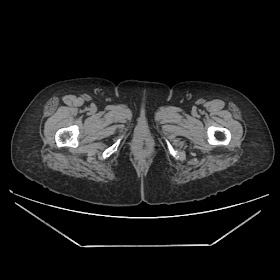

A CT abdomen revealed a left adrenal cortical tumor.

Her abdominal X-ray also reveals a right renal stone although she never complained of renal colic.

Clinician advised against surgery because she was not in pain. Her TSH is normal. A CT abdomen revealed a left adrenal cortical tumor. Diagnosis of pri. aldosteronism was made. Patient is hypertensive since 1995 since her second childbirth. Now BP is normal with medication. She is nondiabetic. Pt. advised to report her Ca2+ and K+ lvl. monthly. Pt. acq. the habit of eating paan (beetle leaf) from her mother in 2011 when she came to stay with her. Used to eat 3-4 paans a day. Stopped in 2013 after Dr. advised against it.

PATIENT'S HISTORY: The patient is a 60-year-old housewife. In 2013, she had an episode of probable stroke followed by nausea, vomiting, diarrhea, weakness, fatigue with loss of appetite, and insomnia. Her legs felt numb. She lost sensation around neck. Had to be admitted to a nursing home. Diagnosis of hypocalcemia and hypokalemia was made. Got discharged after 5 days when k+ and Ca2+ lvl. returned to normal via i.v infusion. For 2 yrs she was fine. In 2015, due to diarrhea and fatigue she got admitted to a Nursing home and stayed there for 7 days. Ca2+ and K+ lvl. was falling, so restored via i.v infusion. This time hypernatremia was also detected. Discharged after her conditions improved. But 2 days later, again due to severe diarrhea had to be admitted to a Nursing home for 19 days. During her stay USG of abdomen, colposcopy and chest X-ray was done. USG detected a large renal calculus measuring 22mm in rt. kidney. Sx was recommended. Pt went to Bhopal for a second opinion.